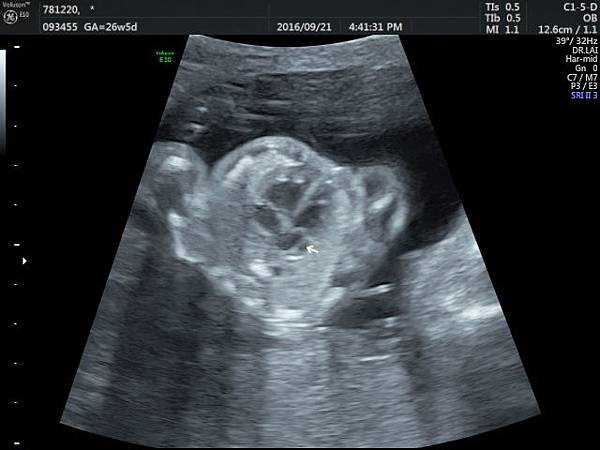

2016年9月21日幫一位懷孕26歲懷雙胞胎的孕婦看胎兒心臟超音波,孕婦目前26週,雙胞胎大小相差四週,高層次超音波除了小的胎兒臍動脈血流有問題之外,沒有其他異常發現,經過我的檢查,我的診斷是小的胎兒有持續性左側上腔靜脈(附圖1~5)。

正常情況左側的上腔靜脈在胚胎發育過程應該要退化,左側頭頸部的靜脈回流是流向右側的上腔靜脈再回到右心房,而持續性左側上腔靜脈是這條血管沒有退化繼續存在,它的血流一般會流入左心房背部的冠狀竇(coronary sinus)再經由冠狀竇回到右心房,因為最終都是回到右心房,理論上沒有什麼問題,只是為何它會不退化呢?是否有什麼因素造成它不退化這才是重點所在,所以做染色體基因檢查的理由就是找出是否有原因。

因為冠狀竇變大,超音波影像常被誤解為心房中隔缺損,兩者的預後差很多,鑑別診斷需要經驗,我常跟孕婦說,如果只給我10分鐘檢查一位胎兒,我會選擇看胎兒心臟,因為心臟就像一部車子的引擎,胎兒先天性心臟病常會合併染色體基因的問題,藉由心臟檢查,可以縮小範圍。

持續性左側上腔靜脈如果沒有合併其他異常,可以視為正常的變異,不需要任何治療,也不會有什麼特別問題,但是如何排除是否合併其他問題呢?我建議需要做染色體及基因晶片檢查,並且需要做高層次超音波排除其他器官是否異常。